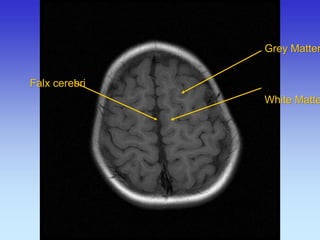

Grey Matter

Superior Sagittal Sinus

White Matter

Grey Matter White Matter

Falx cerebri